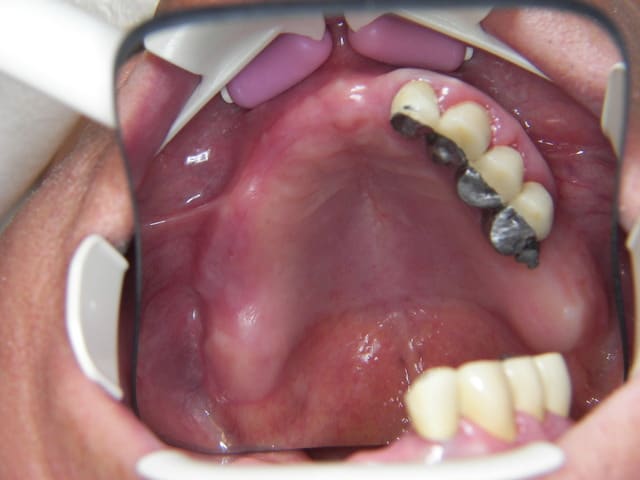

le but c'est de refaire la bouche de la dame, il lui reste fort peu de dent et elle m'a pour le moment posé une limite de budget qui me permet de faire le bas.

en haut j'ai déposé un bridge de 4 dents,(17/16/15/14) et j'ai fait une "augmentation" du sinus par la racine mesiale de 16, (avec un balloon)un comblement de sinus par fenetre latérale n'etant pas envisageable pour le moment.

le patient ne veux que du fixe haut et bas.